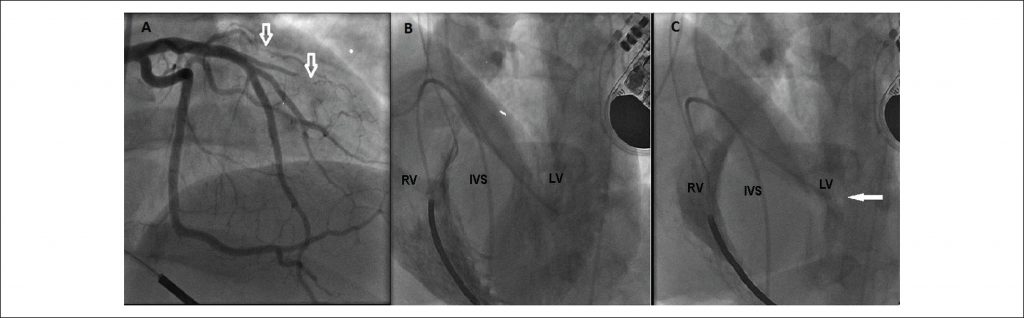

A 35-year-old man sought medical care for recurrent syncope episodes related to moderate exertion in the past 2 months. Upon physical examination, the presence of a rude systolic murmur on the left sternal border was identified. The echocardiogram disclosed a moderate increase in the left atrium and significant hypertrophy of the interventricular septum with an estimated maximum diastolic diameter of 31 mmHg and a maximum left ventricular outflow tract gradient of 56 mmHg. The 24-hour Holter assessment showed the presence of frequent ventricular extrasystoles and an episode of nonsustained ventricular tachycardia. He was prescribed metoprolol 50 mg daily and, based on the high risk of sudden death, received an implantable cardioverter-defibrillator.

Despite the progressive increase in beta-blocker doses, the patient remained quite symptomatic with daily episodes of lipothymia and angina pectoris at minor exertion. Invasive strategy to reduce the intraventricular gradient was planned and the patient underwent a hemodynamic study to better assess the coronary and interventricular septum anatomy. The coronary angiography showed extrinsic compression of the first diagonal branch and septal arteries (). Simultaneous ventriculography of both ventricles disclosed significant hypertrophy of the medial and basal portions of the interventricular septum () with left ventricular outflow tract obstruction (). The isoproterenol infusion during manometry resulted in increased intraventricular gradient from 30 mmHg to 130 mmHg, which revealed an important dynamic obstructive component. The patient was submitted to septal myectomy with no complications, with a significant reduction in the intraventricular gradient.